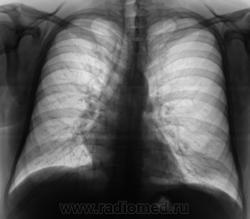

Рентгенограмма в прямой проекции.